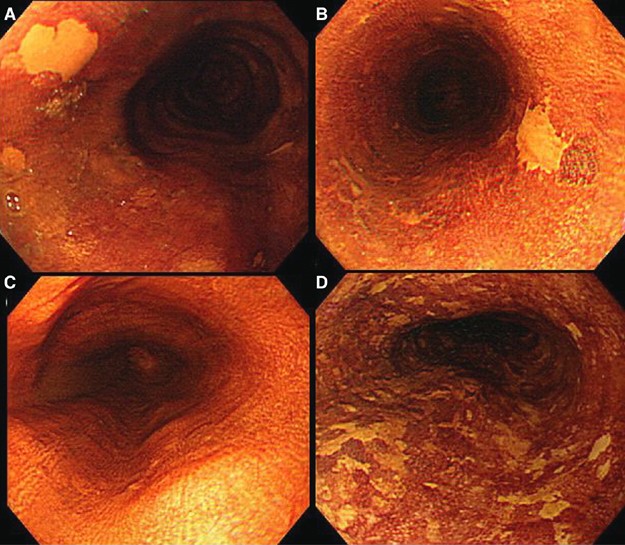

Videoendoscopy (Q240, Olympus, Tokyo, Japan) following Lugol solution spraying was performed on all oesophageal cancer-free subjects who matched the recruitment criteria. After ordinary endoscopic observation, 5–10 ml of 2.0% glycerin-free Lugol's iodine solution, which was a brown liquid consisting of 2.0 g potassium iodine and 4.0 g iodine in 100 ml distilled water, was sprayed from the gastroesophageal junction to the upper oesophagus using a plastic spray catheter (washing tube PW-5L; Olympus, Tokyo, Japan) passed through the biopsy channel of the endoscope. The whole oesophagus was observed again and epithelial areas were categorised as unstained, normally stained, or overstained. We defined LULs as those areas either staining less intensely than normally stained epithelium or completely unstained (Figure 1A–C); this group of lesions included carcinoma, dysplasia, and oesophagitis. When 10 and more than 10 LULs were detected in one endoscopic view, we defined them as multiple LULs (Figure 1D). Biopsies were taken under endoscopic guidance for LULs and paired normal Lugol staining background epithelium. The background epithelium specimens were obtained 1–5 cm away from LULs. We confirmed that samples were correctly taken from LULs during endoscopic observation. Histologic diagnosis among normal epithelium, oesophagitis, BCH, dysplasia, and carcinoma was made according to previously described definitions (Dawsey et al, 1994). Histologic features were evaluated by a pathologist in our hospital.

(A) Endoscopic findings of a Lugol-unstained lesion. This lesion was completely unstained. The lesion was oval and 4 mm in diameter. (B) Endoscopic findings of a Lugol-unstained lesion. This lesion was completely unstained. The lesion was irregular in shape and 6 mm in diameter. (C) Endoscopic findings of normal Lugol staining epithelium without a Lugol-unstained lesion. (D) Endoscopic findings of multiple Lugol-unstained lesions. Many irregular lesions that were stained less intensely than normal Lugol staining epithelium were located in one endoscopic view.